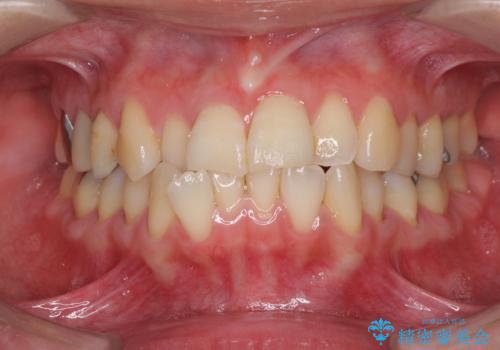

切端咬合をインビザライン矯正で解消

- 前歯のデコボコを気にして来院された患者様です。

上下前歯の先端同士が接触する切端咬合であったため、上顎は歯列を拡大し、下顎はIPR(歯と歯の間を削る)により叢生を解消しながら歯列を小さくすることとしました。

矯正装置にはインビザラインを用いることとしました。

治療途中に前歯に歯髄充血を思わせる痛みが認められたため、無理のない歯の移動と頻繁な経過観察を行いました。

切端咬合はスムーズに解消され、前歯の負担を軽減させることができました。